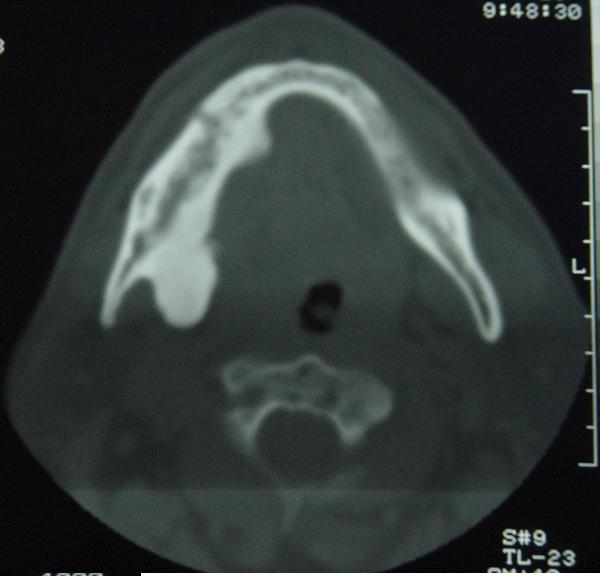

标题: CT12465:下颌骨肿瘤,请会诊 [打印本页]

标题: CT12465:下颌骨肿瘤,请会诊

发现下颌骨肿瘤近30年.逐渐增大.

考虑右侧下颌骨水平部及升部骨纤维异常增殖症可能性大。